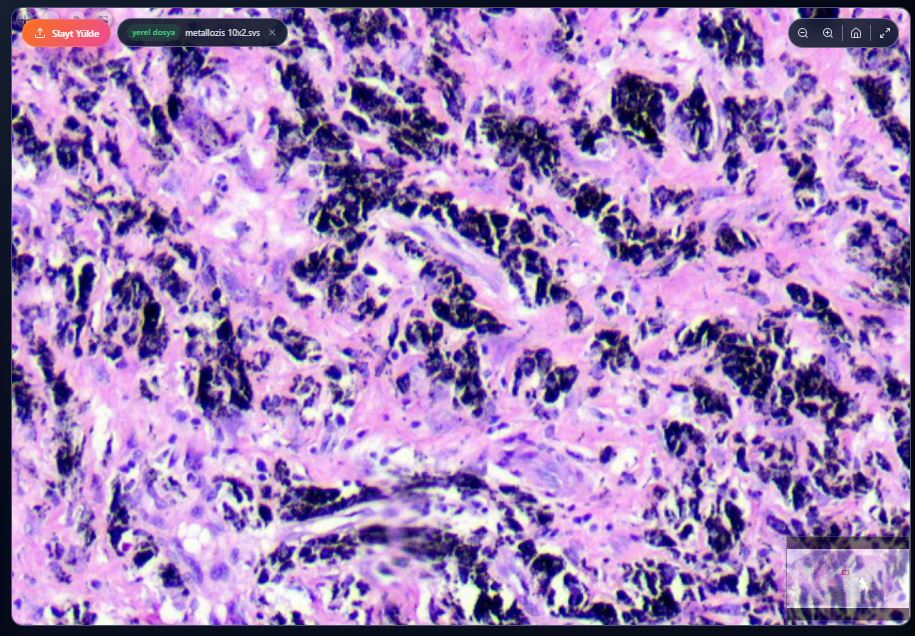

Metalosis Metal pigmenti içeren makrofajlar. Yoğun siyah renkli. Işığı kırmayan oldukça ince partiküller. Metal sanki eğelenmiş ve çöpçü makrofajlar onları yutmuş.